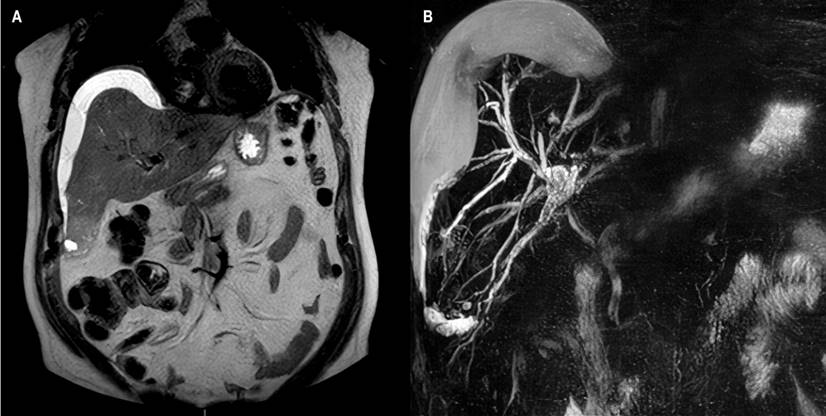

The patient underwent an abdominal ultrasound that described dilation of the bile duct with these measurements: the right route (5 mm), the left one (4.8 mm), and the confluence (5.3 mm). A low amount of gas was also described at the level of the intrahepatic bile ducts. He also underwent a magnetic resonance cholangiopancreatography where they found a focal alteration in the subcapsular region of hepatic segment VI with an image of 34 x 31 x 37 mm, of heterogeneous content and similar images of smaller size, 10 and 13 mm, in segment VIII, suspicious of abscesses. Hepatic subcapsular fluid was also documented in the right lobe (112 mL) (Figure 1) and intrahepatic bile duct dilation with images of microlithiasis in the right hepatic duct near the confluence and in the intrapancreatic segment of the common bile duct. After 48 hours, an abdominal MRI was performed, and an increased volume of the hepatic subcapsular collection was found (Figure 2), so the patient was inserted into a multipurpose catheter. In the procedure, 1600 mL of purulent biliary-looking fluid was drained. The patient continued for five days with biliary drainage of 350-500 mL daily through the multipurpose catheter and with signs of an inflammatory response, so he was taken to ERCP.

Figure 1 Magnetic resonance cholangiopancreatography. A. In sequence T2, subcapsular collection: bilioma. B. 3D reconstruction of the bile duct. Image Archive of Hospital Universitario Hernando Moncaleano Perdomo in Neiva.